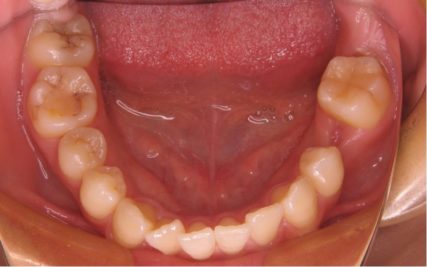

- 治療前

- 上下とも前歯のスペース不足が認められた。歯のサイズと顎の幅とのバランスが不調和な事が原因の1つとして考えられる。

- 治療後

- 前歯部のでこぼこが解消され、正常咬合を獲得する事が出来た。又、歯科矯正用アンカースクリューを用いる事で抜歯スペースを有効に利用できた。